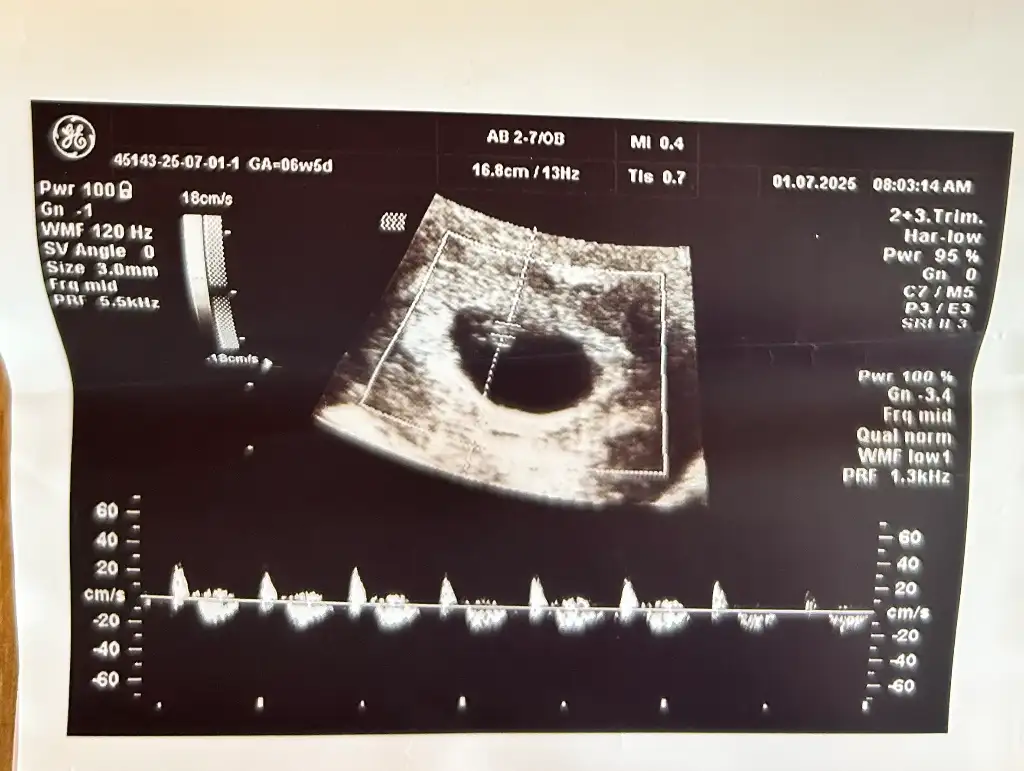

benim anladıgım kadarıyla bebek sag ustte durdugu için kız yorumları gelicekBanada yorum yaparmısınız 6+1 vajinal ultrason görüntüsü

Yorum gelsinde sağlıklı olsun önemli değilbenim anladıgım kadarıyla bebek sag ustte durdugu için kız yorumları gelicek![]()